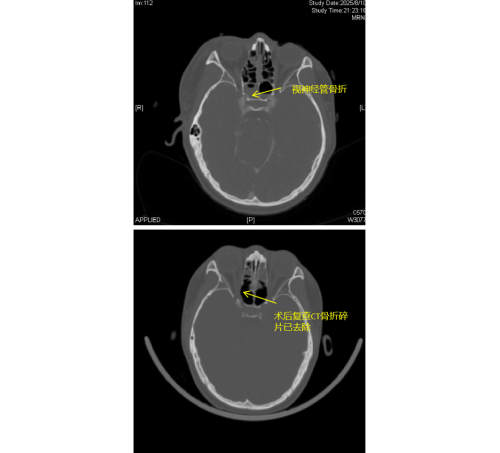

患者李琦(化名)是一名17岁少年,夜间骑电动车不慎撞上路边栏杆,随即出现右眼视力骤降、头痛头晕等症状,被120紧急送入维多利亚老品牌76696vic(南华大学附属长沙中心医院)急诊科。经检查发现,李琦存在颅底多处骨折、面颅多发骨折,尤其危急的是右侧视神经管骨折,碎裂的骨片直接压迫视神经及邻近的颈内动脉,导致右眼瞳孔散大、对光反射消失,视力完全丧失,病情极为危重。

由于视神经管周围解剖结构复杂,上方毗邻前颅底,下方紧邻颈内动脉和海绵窦,稍有不慎就可能导致脑脊液鼻漏、视神经断裂甚至颈内动脉破裂出血等严重后果,因此视神经的特殊位置被视为“手术雷区”。加之操作空间小,手术难度大,对于医生而言是一个巨大的挑战。视神经与鼻窦相邻,用鼻内镜经鼻窦进行视神经管减压手术,视野清楚、损伤最小。在手术过程中,康晓明医生利用高清鼻内镜,精准地清除了压迫视神经的骨折碎片,有效降低了神经压力。

手术完成后即刻观察到李琦右眼对光反射恢复灵敏,经过系统的治疗,其右眼视力已恢复至0.1,术后效果显著。目前,李琦正在进一步康复治疗中。此类高难度手术的成功,不仅展现了医院在多学科协作和急重症救治方面的综合实力,也为复杂颅底外伤患者带来了新的希望。